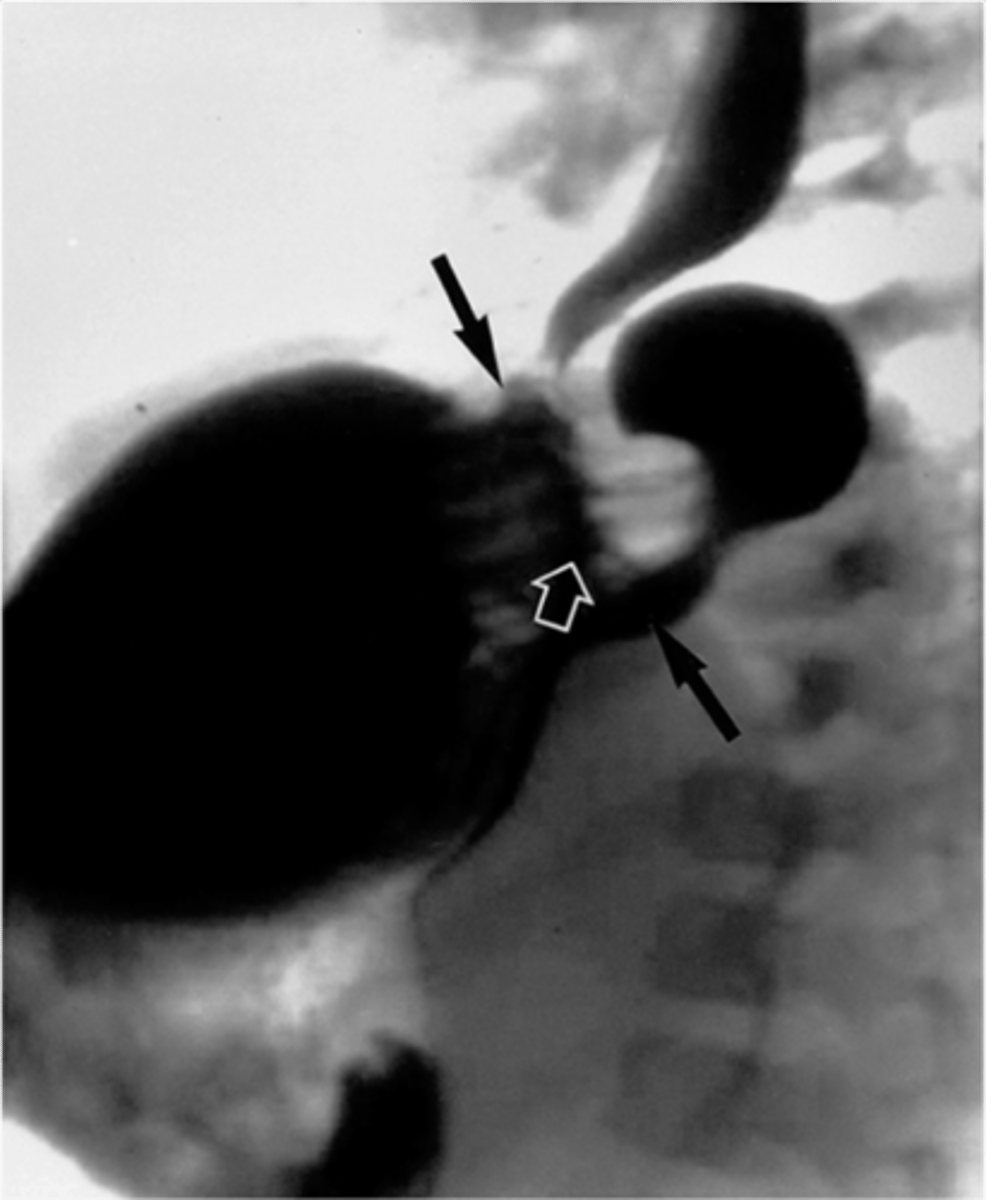

ulcer

Ulcer (pic 2)